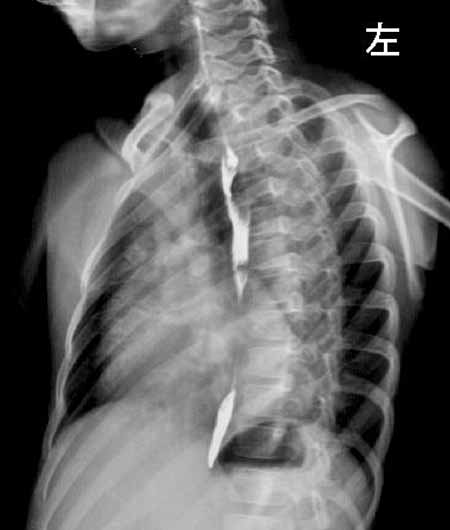

x线特点:主动脉型心脏,左室增大为主,主动脉增宽;肺动脉增粗。

结果收到,大家都没有猜对,法四学习了!肺内出现粗乱血管影或中下肺野及肺门附近有网状血管纹理,为体动脉侧支循环的表现,提示中度肺动脉狭窄。